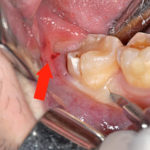

Жалобы на то, что целый зуб зарос десной, не всегда описывают реальное положение вещей. Такой зуб часто лишь выглядит здоровым, но при тщательном стоматологическом осмотре в нем обнаруживается кариозная полость в участке, который не просматривается без специальных инструментов. Чаще всего гиперплазия десен развивается при контактном кариесе или кариесе шейки зуба.

В первом случае интенсивный рост тканей начинается с десневого сосочка — приподнятого и заостренного участка десны, который «вклинивается» между двумя соседними зубами. Во втором случае гипоплазия десны берет свое начало на фронтальной поверхности в том месте, где находится кариозная полость — зуб начинает зарастать снизу вверх, что наиболее заметно по сравнению с высотой соседних десен.

В обоих случаях причиной этого состояния становится воспалительный и инфекционный процесс в деснах, обусловленный кариесом и присутствием в отдельном участке десны постоянного источника инфекции (кариозной полости).